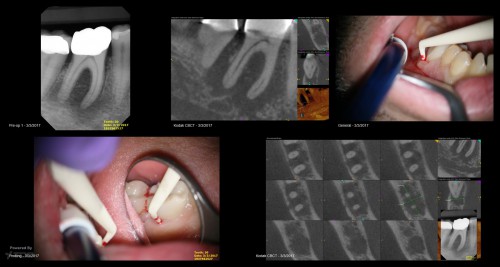

1 yr CBCT Recall

#29 with a deep split in the middle 3rd

By Reuben Joseph / August 27, 2018

Somehow i find these premolars canals that splits in the middle 3rd harder to locate […]